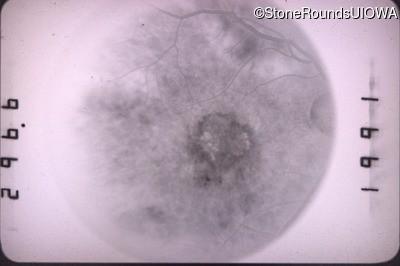

Visit at age: 42 years

Fundus Photography - Right - 20/100 -1

Exemplar

Fluorescein Angiography - Right - 20/100 -1